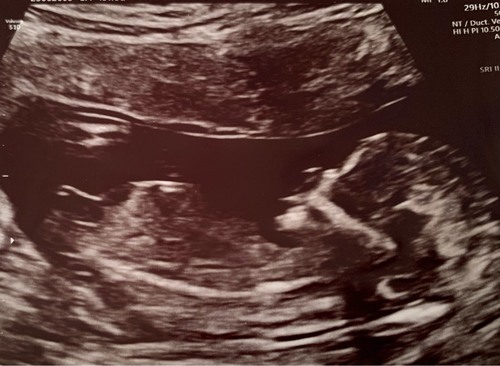

13 weken en 2 dagen zwanger. Wat denken jullie?